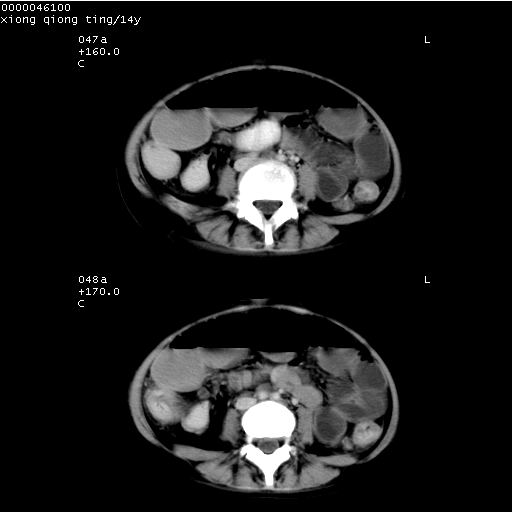

中下腹及盆腔ct轴位平扫+增强扫描(层厚10mm,螺距1.0,重建间隔10mm),图像如下:

(注:患儿检查当日上午9时口服胃肠道对比剂,下午3时许行ct扫描检查,未行对比剂直肠保留灌肠,检查当日患儿腹泻)

中下腹及盆腔ct轴位扫描(ps+ce)提示:腹部肠管明显充气扩张,并见数个不同宽度之气液平面;疑不全性肠梗阻或肠郁张。临床会诊考虑为患儿腹泻,肠郁张所致;后来未经特殊处理,患儿大便恢复正常,亦无腹胀。